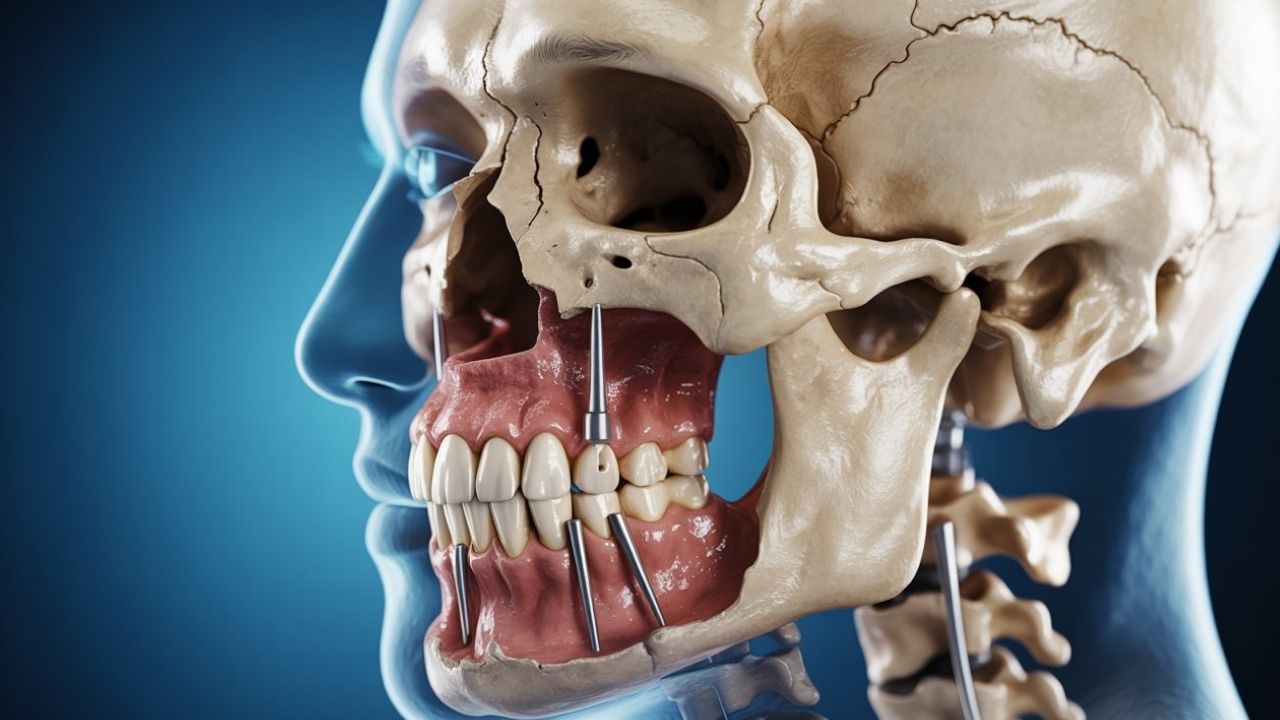

Traditional implants are placed into the jawbone and are ideal when you have adequate bone volume and density. When the upper jaw has resorbed (shrunk) substantially, conventional implants may first require sinus lifts or bone grafting, adding cost and time. Zygomatic implants are longer implants that engage the zygomatic bone (cheekbone)—a denser anchor—so clinicians can restore the upper arch even when the maxillary bone is too thin or soft for standard implants without major augmentation.

Unlike standard implants that rely on jawbone density, zygomatic implants anchor securely into the cheekbone, allowing patients with severe bone loss to restore their smiles without extensive bone grafting. In many cases, this approach can actually save time, reduce the number of surgeries, and offer a long-term cost advantage despite the higher initial fee.

Zygomatic placement requires advanced imaging (CBCT), careful mapping of sinus and zygomatic anatomy, and a surgeon experienced with long, angled trajectories to the cheekbone. This specialized skillset and longer operating time contribute to higher fees.